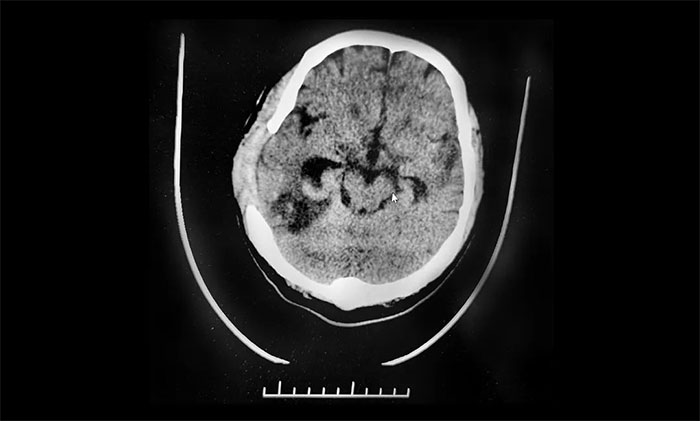

“環(huán)池沒有受壓,CT顯示環(huán)池存在,還有希望!”潘仁龍主任的一番話讓劉叔看到一線生機。最終,劉先生被轉(zhuǎn)入上海藍十字腦科醫(yī)院尋求進一步治療。

環(huán)池在中腦外側(cè)連接于四疊體池和腳間池之間,其內(nèi)有大腦后動脈、小腦上動脈、脈絡(luò)叢前、后動脈、基底動脈和滑車神經(jīng),為腦脊液循環(huán)的必經(jīng)之路。

潘仁龍主任解釋,在顱腦外傷的搶救中,血腫和腫脹腦組織的占位常壓迫腦中線結(jié)構(gòu),導致腦干周圍腦池形態(tài)的改變或消失。這些變化直接影響到腦干的功能,并反映出腦干的受傷程度。在腦干周圍的腦池當中,環(huán)池圍繞于中腦的兩側(cè),在外傷性顱內(nèi)血腫早期或血腫量較少及腦腫脹較輕時,腦干未明顯受壓,CT表現(xiàn)環(huán)池的形態(tài)正;蚧菊!

隨著病情的發(fā)展,腫脹的腦組織或較大的血腫產(chǎn)生了占位效應(yīng),顳葉鉤回及海馬回經(jīng)小腦幕切跡向下疝出,并壓迫中腦,使腦干發(fā)生軸承性或側(cè)方移位,導至同側(cè)瞳孔改變及對側(cè)錐體束陽性體征,中腦平面的網(wǎng)狀結(jié)構(gòu)受壓損傷而產(chǎn)生意識障礙。此時病情較重,CT表現(xiàn)為環(huán)池部分受壓,經(jīng)常在一側(cè)大腦半球可看到腦池呈低密度裂隙,如完全閉塞,將看不到有腦脊液的腦池。

環(huán)池受壓或消失提示顱內(nèi)壓增高危險性增加3倍,死亡率增加2~3倍。

▲ CT顯示環(huán)池存在,還有希望